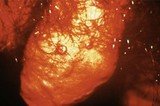

• На слици се види меки шанкр и његови симптоми као полна болест код мушкараца

• Слика приказује меки шанкр и његове симптоме као полно преносиву болест код мушкараца

• На слици се види меки шанкр и његови симптоми као полно преносива инфекција код мушкараца

• Слика приказује меки шанкр и његове симптоме као сексуално преносиву болест код мушкараца